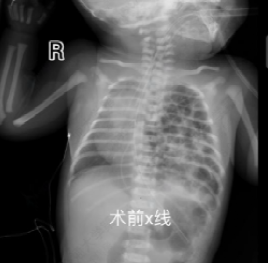

Immediately after birth, the baby developed severe respiratory distress. The neonatology team rapidly performed endotracheal intubation on the delivery table to establish effective ventilation, and the infant was then transferred to the neonatal unit for hemodynamic stabilization. At 24 hours after birth, imaging revealed that a large portion of the spleen and intestines remained herniated into the thoracic cavity, posing an imminent risk of bowel strangulation. In accordance with clinical guidelines, the pediatric surgery team decided to perform minimally invasive thoracoscopic repair. During the operation, Director Cao Zhenjie’s team carried out precise maneuvers in a very limited space, gently reducing the herniated abdominal organs back into the abdominal cavity. Given the large diaphragmatic defect, a biological patch was used to reinforce and repair the diaphragm. With continuous support from the anesthesiology and nursing teams, the procedure was successfully completed. Postoperatively, the infant’s lung function gradually recovered, and the baby was successfully weaned from the ventilator.